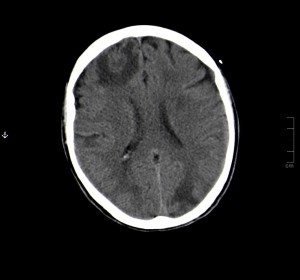

ESTUDIO ACTUAL (Aparición de metástasis cerebrales)

En estos tres últimos cortes axiales craneales, pertenecientes al estudio actual se obseva: aparición de numerosas lesiones focales cerebrales con leve edema en la periferia con distribución bilateral, a nivel cerebeloso y cerebral, la de mayor tamaño se encuentra a nivel frontal derecho y es indicativo de metástasis. No se observa desplazamiento de la línea media.